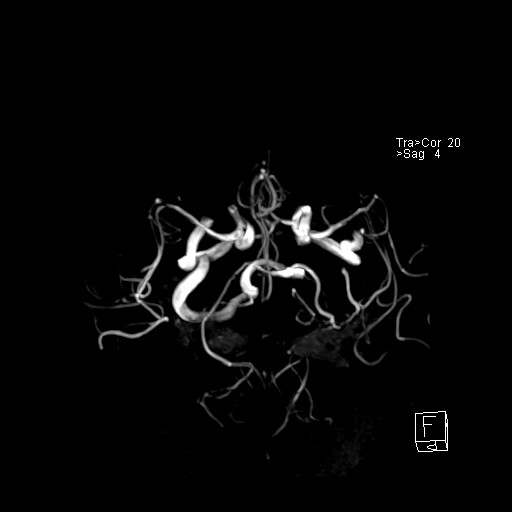

239716 - VILLANUEVA, WILLIAM A. - Number 1 |

|

239716 - VILLANUEVA, WILLIAM A. - Number 1 |